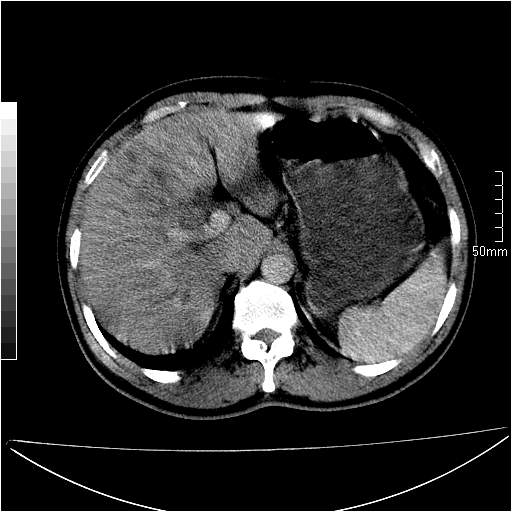

男性,54岁,皮肤黄染,搔痒一周余.b超示肝左叶回声异常.初步诊断1胆总管下段结石2胆囊结石伴慢性胆囊炎请各位战友帮忙看一下肝脏多发低密度如何解释恰当.增强效果不是很好.请大家见谅.

胆总管及肝内胆管扩张,考虑是结石!但,肝内的低密度区增强不明,可能是肝ca,因为肝ca在增强时呈快进快出.另年胆总管扩张原因,可以考虑一下是不是,胆管ca.再次要考虑肝内的低密度是否为海绵状血管瘤所致!

首先,胆总管下端结石梗阻伴肝内胆管扩张可确定。

其次,增强动脉期肝静脉显影,肝实质密度不均。——此为右心功能不全引起肝淤血的表现。

另外,肝八段低密度占位,呈多灶性,考虑肝脓肿或肝癌可能,(图像质量欠佳)建议进一步检查。